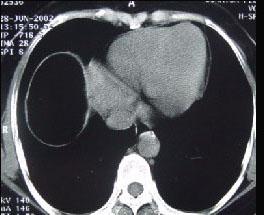

男,30岁,右下腹稍隆起,CT检查如图,最可能的诊断为 ( )A.右膈下脓肿B.间位结肠C.右膈下脂肪瘤D.右下肺肺大疱E.右下肺炎

问题 男,30岁,右下腹稍隆起,CT检查如图,最可能的诊断为 ( )

选项 A.右膈下脓肿 B.间位结肠 C.右膈下脂肪瘤 D.右下肺肺大疱 E.右下肺炎

答案 C